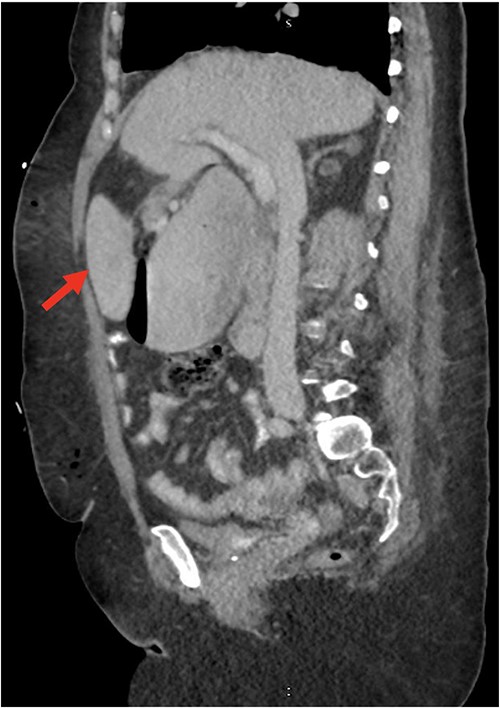

Despite the insertion of the NGT yielding 1500 cc output in 24 hours, the patient continued to experience severe abdominal pain. Urgent abdominal and pelvic computed tomography (CT) scans were taken, as seen in Figs 2–4. The CT scans showed gastric distension and the spleen positioned anteriorly in the right upper quadrant. Consequently, the decision was made to promptly bring the patient to the operating room for a diagnostic laparoscopy with plan to detorse the spleen.

CT of the abdomen and pelvis (sagittal slice) showing gastric distention and the spleen positioned anteriorly.